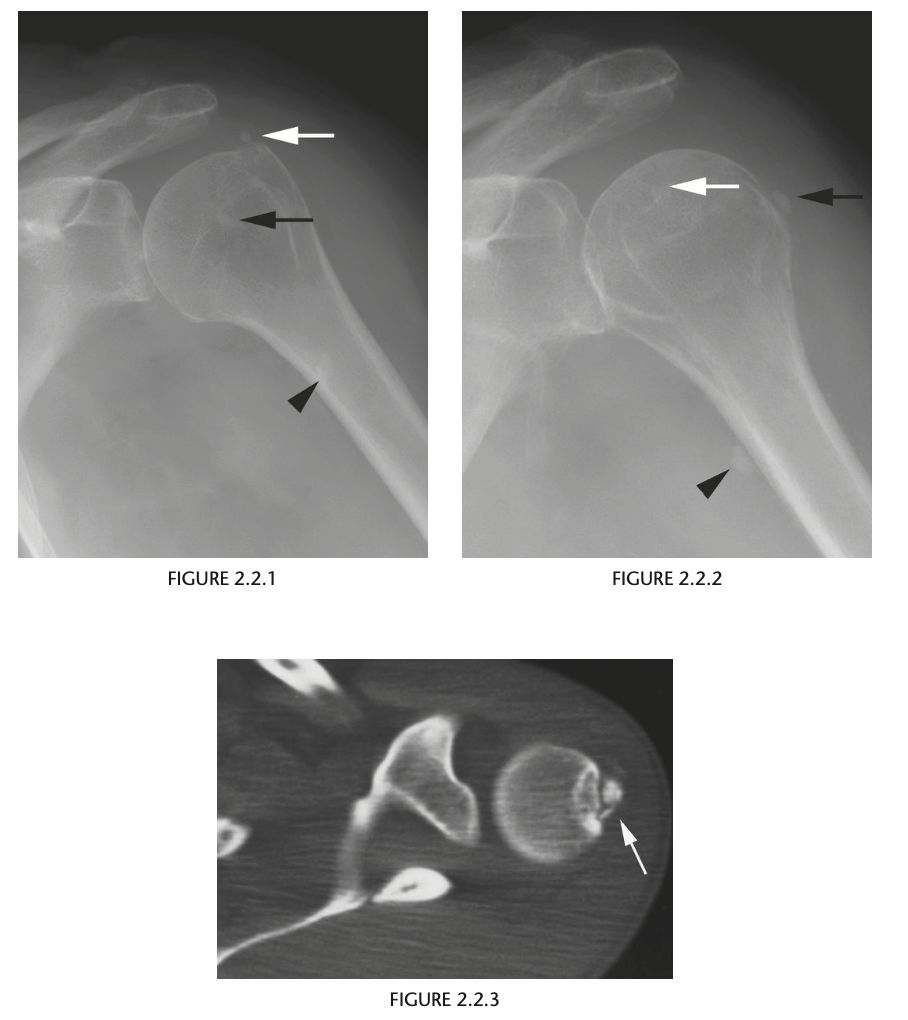

61yr old woman with shoulder pain

AP Radiograph of left shoulder in external and internal rotation (1 & 2) - globular foci of calcification in expected location of supraspinatus (White arrow) and infraspinatus (black arrow) and pectorals major

DIAGNOSIS: Hydroxyapatite deposition disease

(HADD)

HADD consists of crystal deposition in

and around joints, without a known cause.

AKA calcific tendonitis

On radiographs, the calcium deposits appear cloud-

like and amorphous and can involve the tendon,

ligament, bursa, or joint capsule. Intraarticular crys-

tal deposition can destroy the joint space, resulting

in a condition referred to as “Milwaukee shoulder.”

On CT,

­ accompanying erosion of the underlying bone can be

seen. CT appearance has been described as commonly

having a flame-shaped or comet-tail configuration of

the calcifications

If not in shoulder/region not common for HADD ?Malignancy